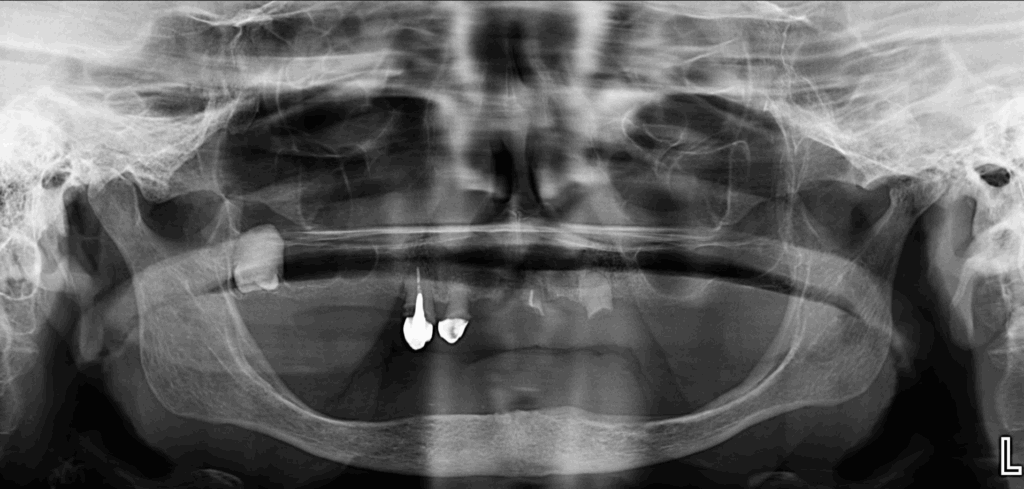

En la radiografía panorámica (Figura 1), se aprecia aplanamiento del contorno del cóndilo mandibular izquierdo, neumatización alveolar de los senos maxilares, edéntulo parcial en maxilar superior y edéntulo total en maxilar inferior, presencia de corona con falta de sellado, espigo y obturación sub extendida de conducto en pieza 13, corona protésica con falta de sellado en pieza 12, remanentes radiculares en piza 21 y 23. Siendo lo más resaltante la pieza 18, la cual esta retenida en posición vertical con un aumento de la densidad radicular.

Radiografia Panorámica